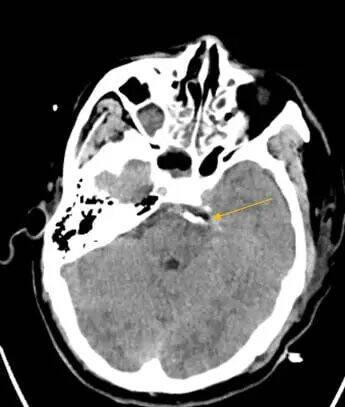

这一手术入路堪称神经外科手术的“高难度赛道”:手术区域深窄,视野暴露受限,术中操作空间极小,稍有不慎就可能损伤面听神经引发面瘫、听力障碍,或触碰脑干导致呼吸循环紊乱,手术风险极高。为确保手术万无一失,团队术前反复研读影像学资料(图1),并急诊先由主治医师张晓东、徐坤和耿仁强行脑血管造影(图2),依托神经介入指引精准标记出动脉瘤的位置、大小及与周边组织的毗邻关系;争分夺秒完善相关准备工作后行开颅动脉瘤夹闭术,术中在高倍手术显微镜下,以毫米级精度仔细分离蛛网膜粘连,小心避开神经血管“禁区”,精准选择适配的动脉瘤夹,成功将动脉瘤颈完全夹闭(图3术中动脉瘤夹位置)。术后复查头颅CT(图4)显示,动脉瘤夹位置精准,动脉瘤无残留显影,周围血管神经未受任何损伤。

术前颅脑CT显示蛛网膜下腔出血;